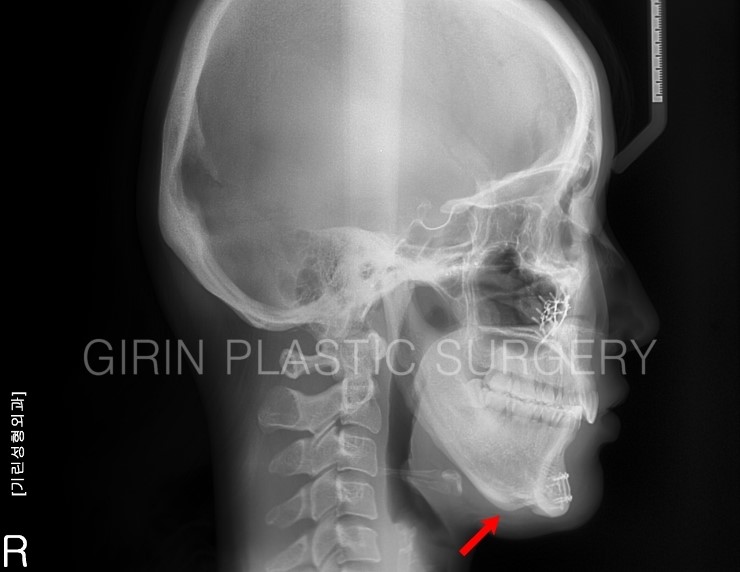

육안으로 봤을 때 앞턱이 갸름하지 않고 U라인으로 보입니다. 엑스레이를 보면 티절골 후 발생한 이차각이 확인되는데 옆모습을 보면 좀더 확실히 증상이 나타납니다.

화살표부위가 이차각이며, 귀밑각이 과절제되었습니다. 재수술로 이차각을 포함한 앞턱까지 전체적인 라인수정 필요성이 있습니다.